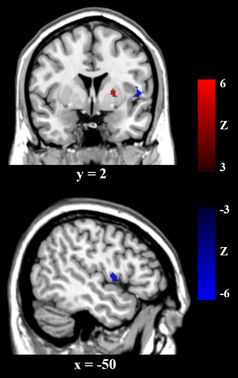

虽然这些结果已经表明了大脑结构上的差异,但是这些差异不能代表功能上的差异。发表在《Addiction Biology》上的论文则采用线索任务和功能成像分析考察了LOL组和正常组在功能上的差异,该论文还紧密联系脑岛皮层——一个在成瘾行为中具有重要作用的脑区——进行。在线索任务中,我们给被试呈现游戏相关的视频和一些控制视频。结果发现LOL视频会引起更强的奖赏系统激活,以及更弱的前额叶皮层激活,IGD评分与右腹纹状体的活动呈正相关,与右背外侧前额叶皮层(DLPFC)的活动呈负相关。游戏剥夺状态会导致脑岛区域的活动增加,采用左侧脑岛作为种子点,PPI的分析发现其与纹状皮层有正联结,而与DLPFC负联结,这说明脑岛在其中起到了平衡两个系统的作用。这个结果与之前团队在Frontiers in Psychiatry上发表的以《A Tripartite Neurocoginitive Model of Internet Gaming Disorder》为题的理论文章的预期一致。

图2:采用左侧脑岛作为种子点,PPI的分析发现其与纹状皮层有正联结,而与DLPFC负联结,这说明脑岛在其中起到了平衡两个系统的作用。